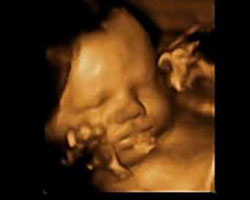

Aqui tens imagens que temos a certeza que vais adorar: uma ecografia de 37 semanas de gestação, bem como um fantástico vídeo no qual poderás ver o movimento do bebé no útero. Não percas!

Ecografia de 37 semanas